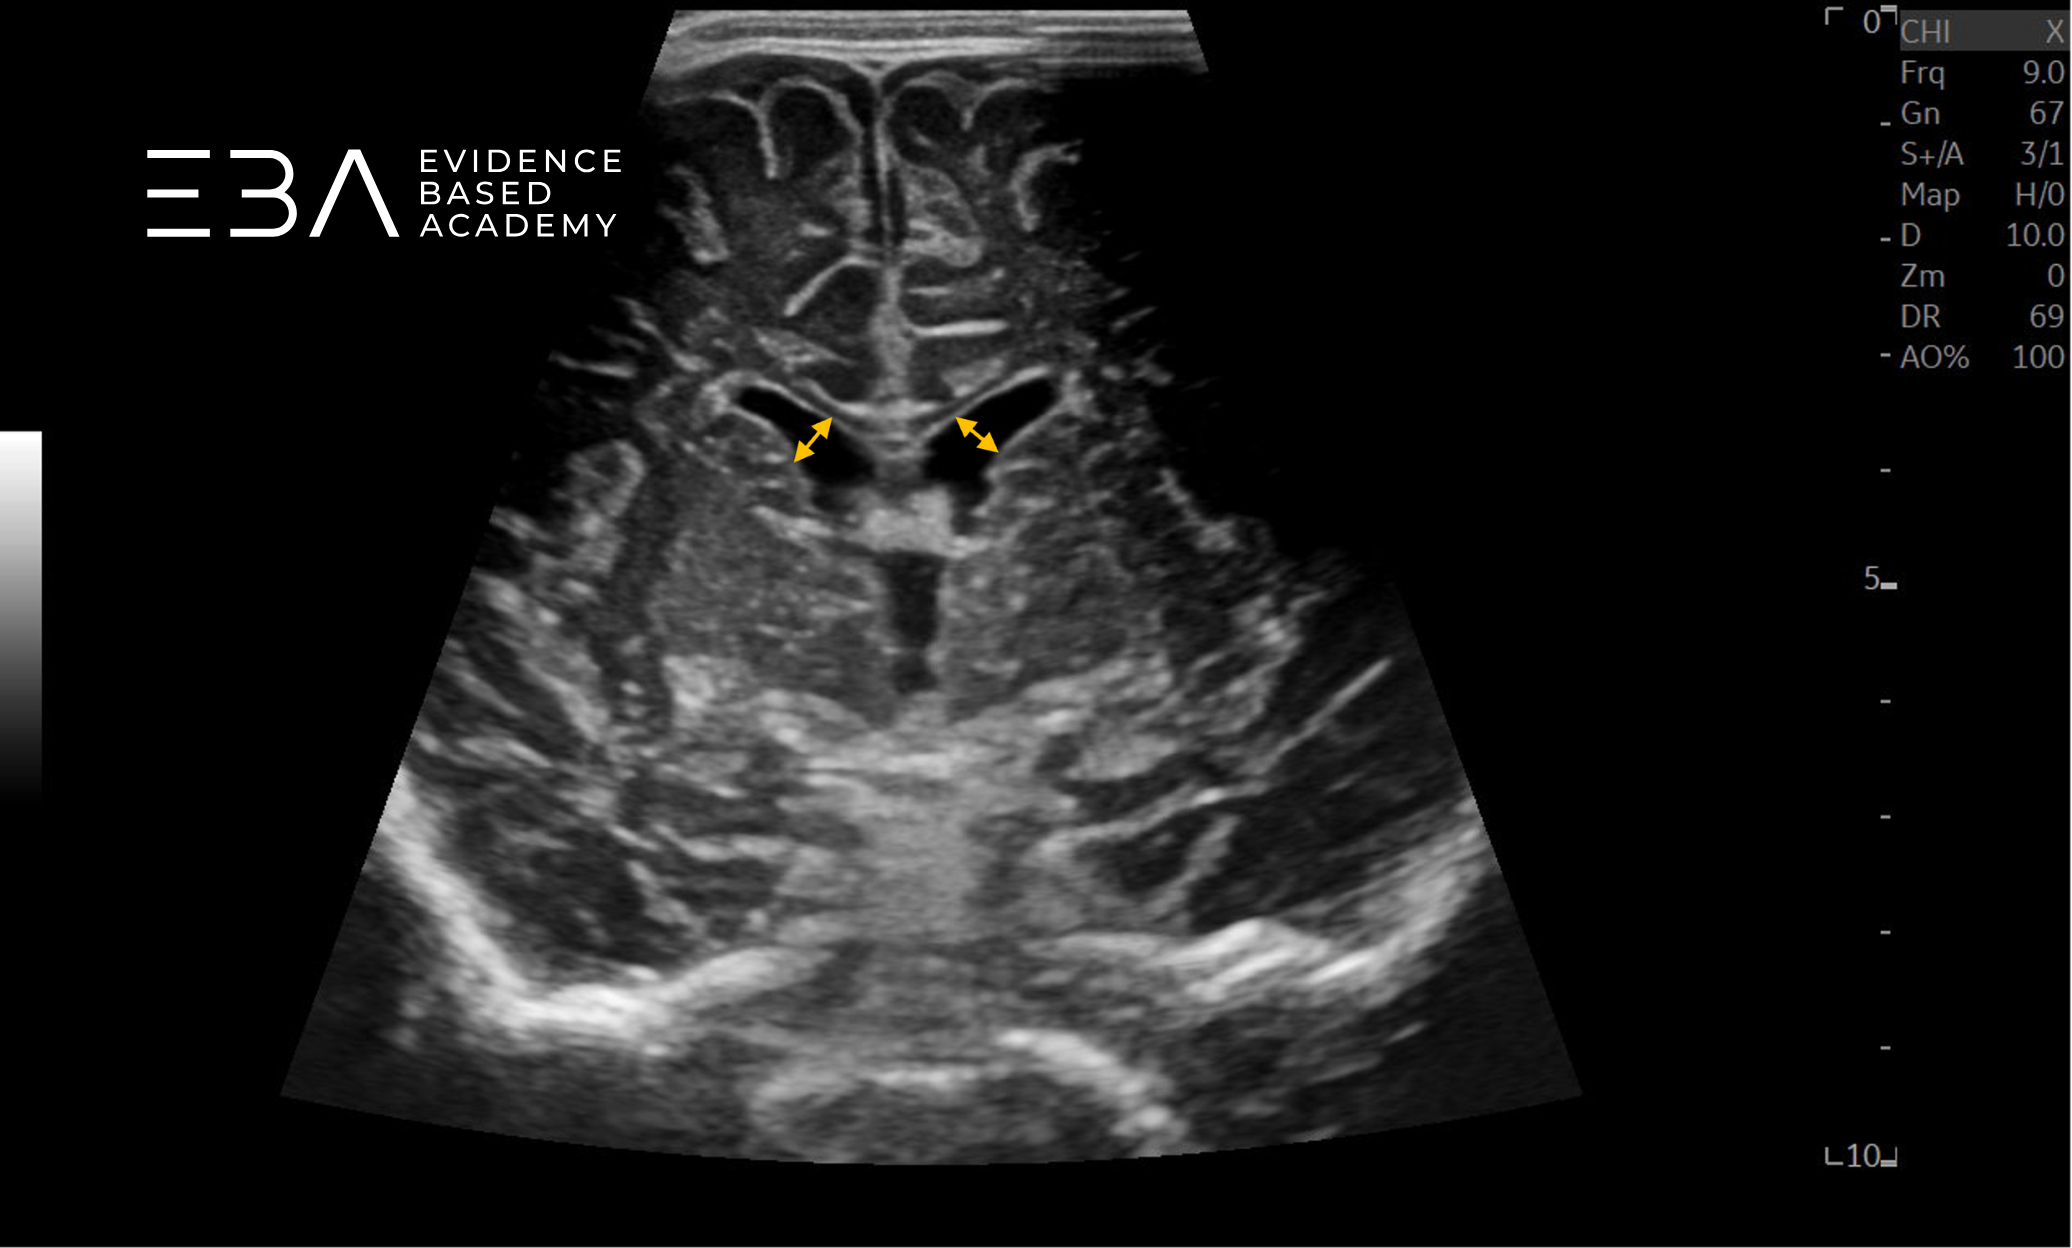

Projekcja 3 – na poziomie wzgórza: widoczne są bruzdy boczne, strop komory trzeciej i płaty skroniowe. Jądra ogoniaste tworzą ściany boczne układu komorowego, ciało modzelowate — strop, a przegroda przezroczysta – ścianę przyśrodkową. Komora trzecia jest cienką bezechową strukturą pośrodkową między wzgórzami. Poniżej leżą struktury pnia mózgu (3, 6).

zdj. 13

Głowica sektorowa. Żółtymi strzałkami zaznaczono rogi czołowe komór bocznych, czerwoną strzałką zaznaczono śródmózgowie.